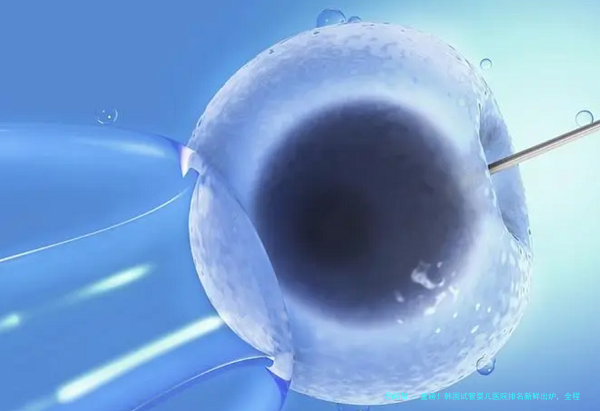

为帮助有辅助生殖需求的家庭科学择院、合理规划预估,结合2025年医疗数据与产业界调研,现发布《韩国试管婴儿医院排名及全程费用明细》,实质威望、结构明了,给对照。

| 取卵手术 | 2-3 | 含麻木、实践室操作 |

| 胚胎培养(含ICSI) | 2-4 | 囊胚培养另计 |